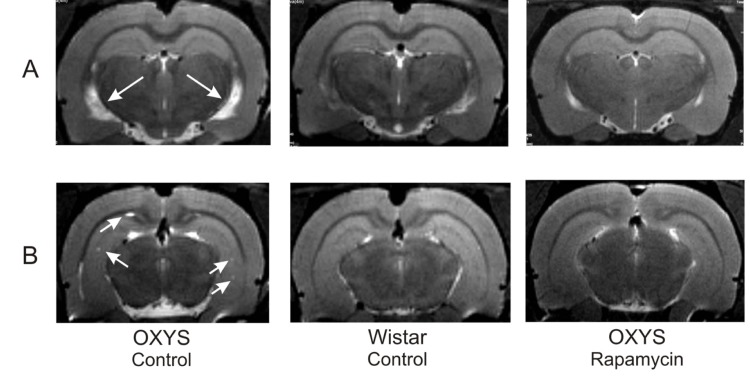

MRI revealed hydrocephalus in control group of OXYS rats (Table 1). The area of the lateral ventricles was about 2 times greater than that of Wistar rats (F1,10=17.12, p<0.002 in relative and F1,10=21.12, p<0.001 in absolute values). Rapamycin treatment eliminated the difference between rapamycin-treated OXYS and control Wistar rats in these parameters.

We had detected no loci of demyelination in the brain of Wistar rats. At the same time, 100% of OXYS rats from control group showed signs of neurodegeneration, which was manifested by loci of demyelination. Rapamycin supplementation decreased the percentage of animals with demyelination to 50±20% (F1,10=10.00, p<0.010). The number of loci in control OXYS rats was 4 times higher than in rapamycin-treated animals (F1,10=14.76, p<0.003).

In agreement with our previous reports, here we described that 3-months-old OXYS rats displayed lower locomotor and exploration activities in the OF and a higher level of anxiety in the EPM tests in comparison with Wistar rats. Rapamycin treatment from the age of 1.5 months partially prevented the behavioral decline of OXYS rats. This improvement of behavior can be explained by normalization of the brain structure revealed by MRI. We demonstrated that rapamycin decreased the size of enlarged hypocampus, prevented hippocampal demyelination and decreased the volume of the lateral ventricles. Importantly, rapamycin abrogated hydrocephalus. It was shown that enlargement of ventricles is associated with accumulation of β-amyloid in the brain [44]. However we observed neither accumulation of β-amyloid nor effect of rapamycin. Instead, rapamycin decreased Tau phosphorylation, which was increased in control OXYS rats compared with Wistar rats. Noteworthy, rapamycin treatment decreased Tau phosphorylation in both rat strains. Tau is a microtubule-associated protein, which is widely expressed in neurons [45]. An increase of Tau phosphorylation and aggregation is toxic for neurons, causing nurodegeneration [46-49]. Also, tau phosphorylation impairs presynaptic function in hypertriglyceridemic mice [50].